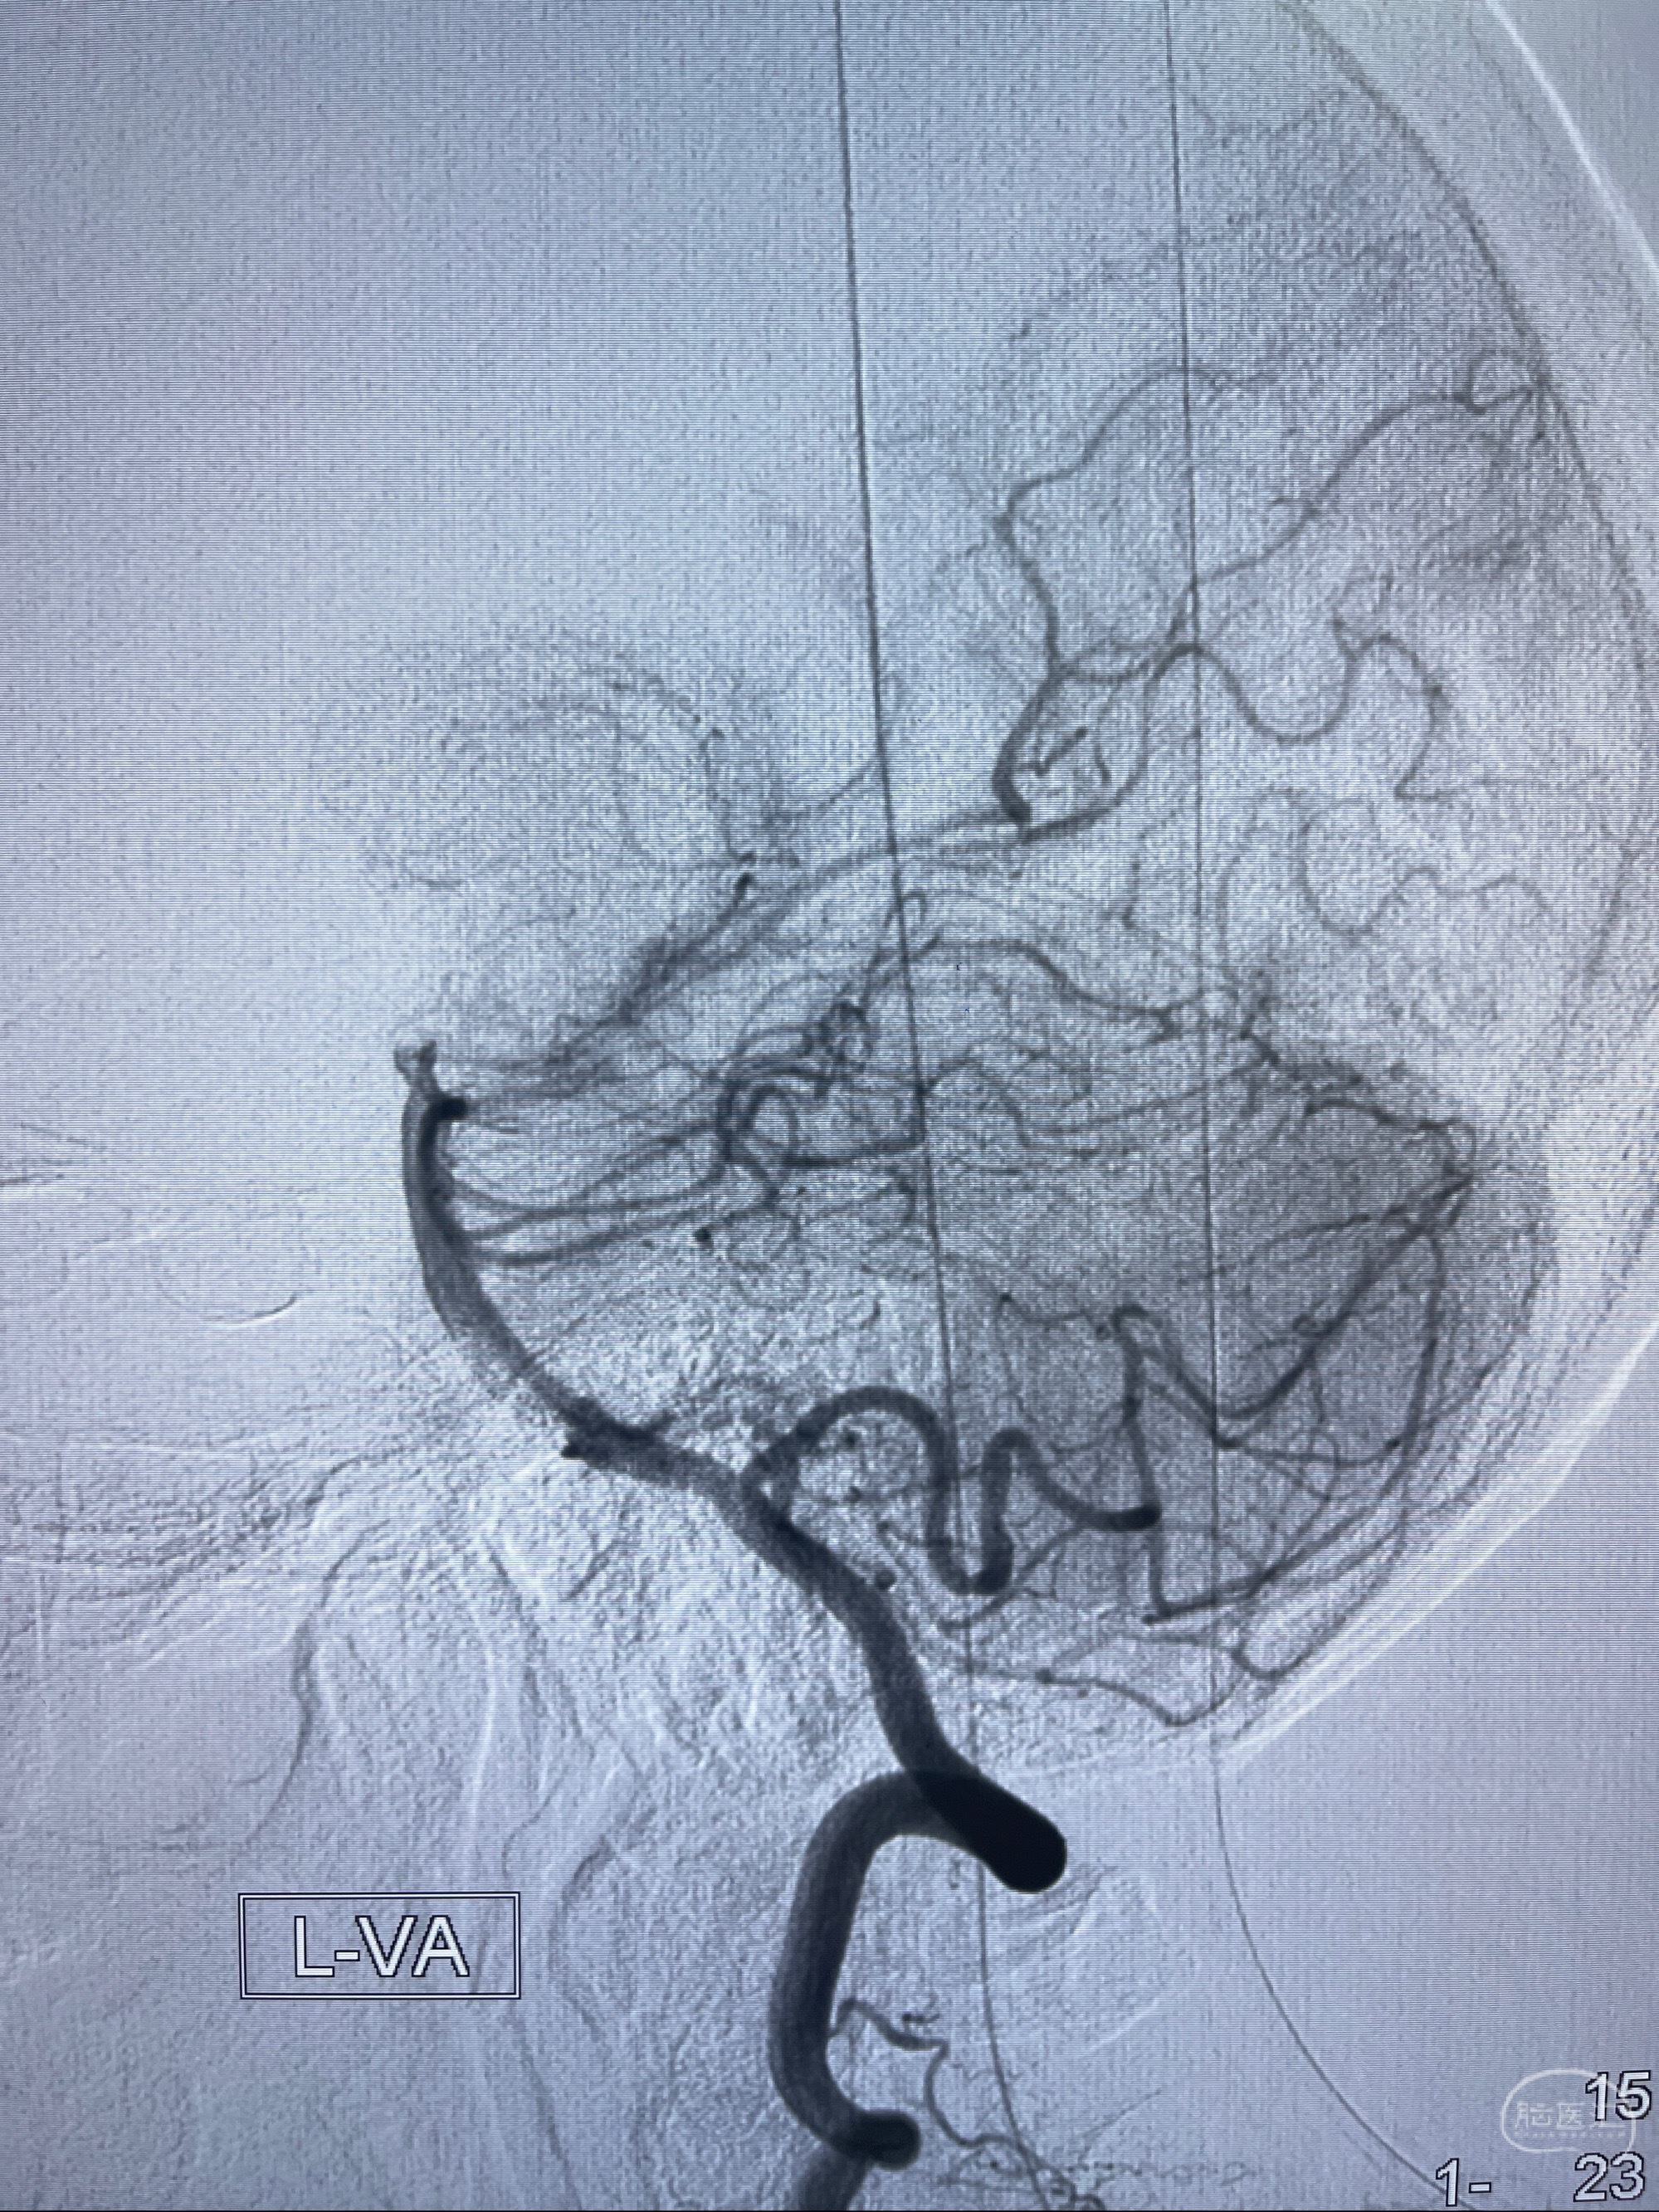

检查;2023-7-18 抚州市第一人民医院 头颈部CTA:左侧大脑前动脉A2段动脉瘤,左侧颈内动脉C4段轻度狭窄,右侧颈内动脉C6段中度狭窄

1.左侧大脑前动脉远侧段(A2-A5)动脉瘤

2023-08-23DSA:左侧前交通动脉瘤,左侧A3/4交界处多发动脉瘤